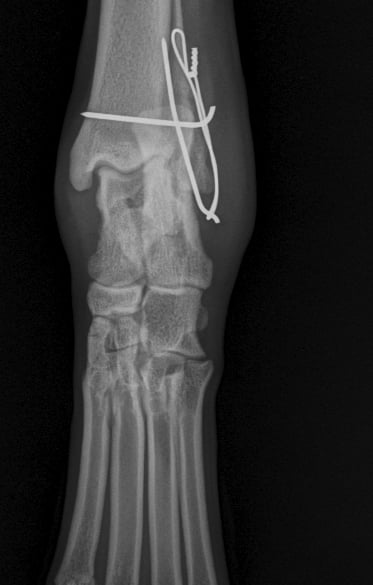

Orthogonal xrays reveal a lateral malleolus fracture (Fig.1 and 2), stress views and palpation revealed stable joint with no affection of collateral ligaments but due to the fracture there is some degree of rotational instability. Surgical stabilization is strongly advised as Buddy is a 40 kg patient.

Fig. 2

Fig. 1